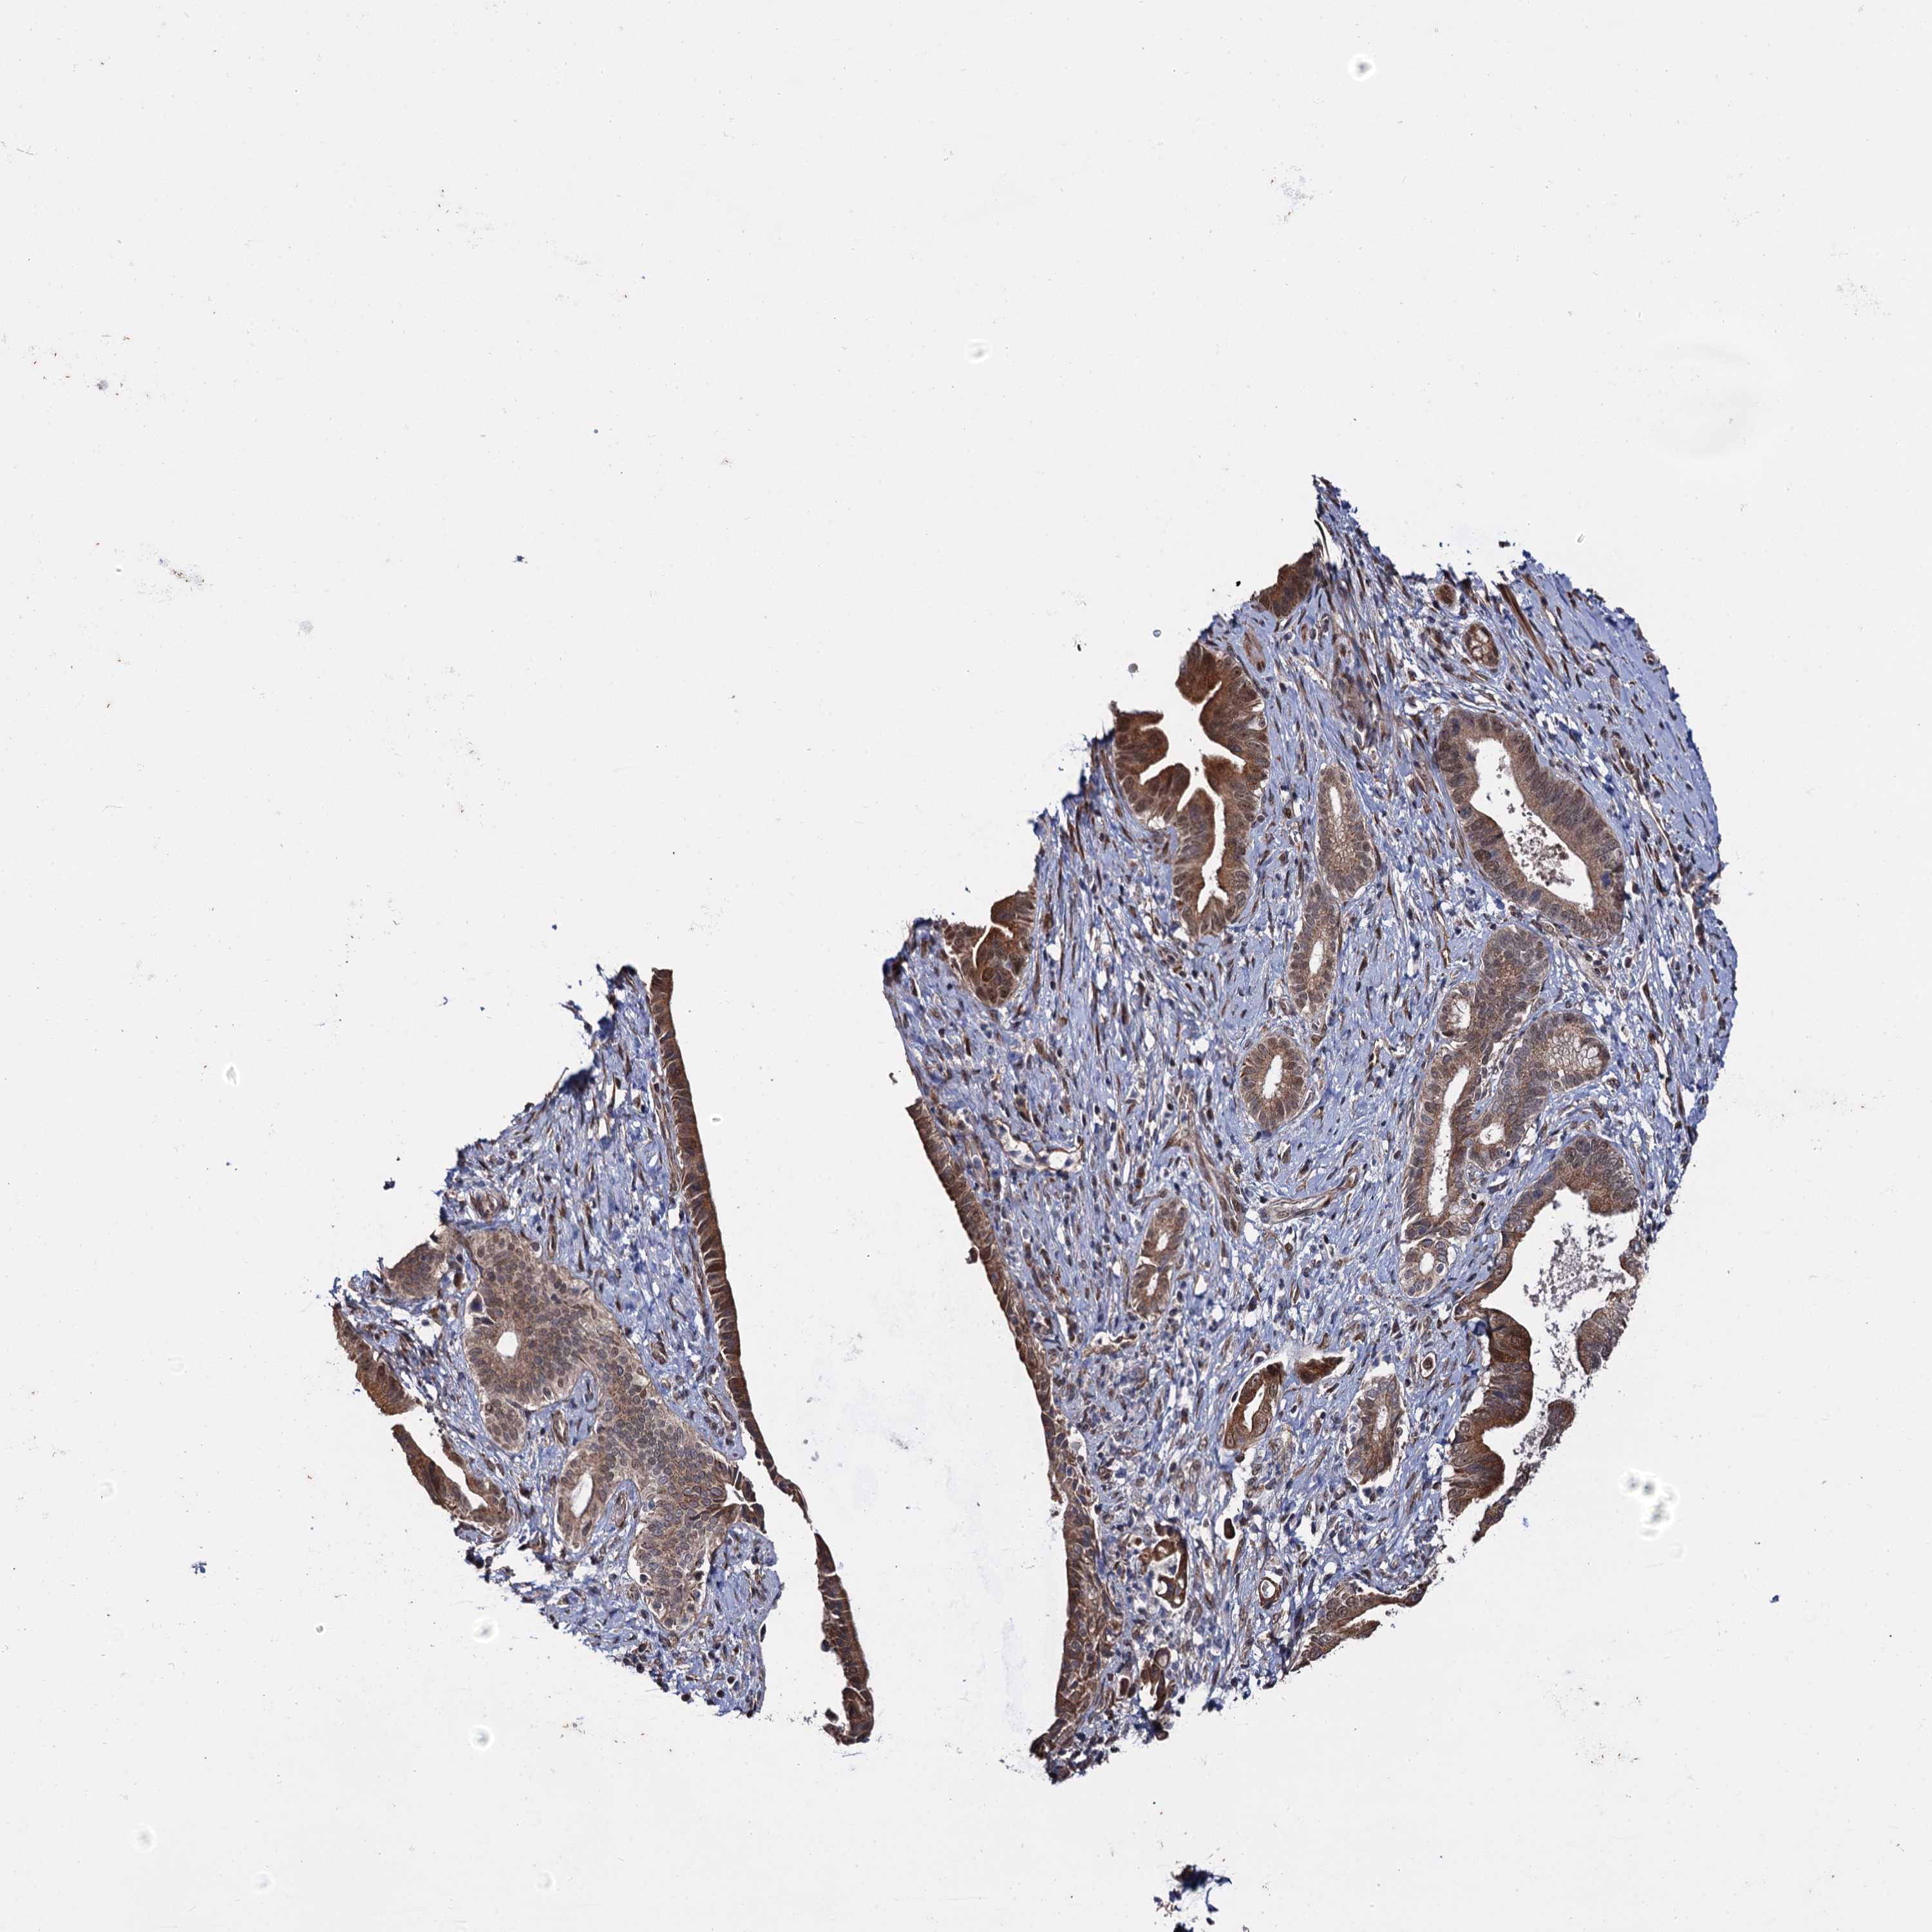

PANCREATIC CANCER - Protein expressioni

A mouse-over function shows sample information and annotation data. Click on an image to view it in a full screen mode. Samples can be filtered based on level of antibody staining by selecting one or several of the following categories: high, medium, low and not detected. The assay and annotation is described here.

Note that samples used for immunohistochemistry by the Human Protein Atlas do not correspond to samples in the TCGA dataset.

Antibody stainingi

Antibody staining in the annotated cell types in the current human tissue is reported as not detected, low, medium, or high, based on conventional immunohistochemistry profiling in selected tissues. This score is based on the combination of the staining intensity and fraction of stained cells.

Each image is clickable and will lead to virtual microscopy that enables deeper exploration of all samples and also displays staining intensity scores, fraction scores and subcellular localization as well as patient and tissue information for each sample.

Antibody HPA039318

Antibody HPA039763

Staining

High

Medium

Low

Not detected

Intensity

Strong

Moderate

Weak

Negative

Quantity

>75%

75%-25%

<25%

None

Location

Nuclear

Cytoplasmic/membranous

Cytoplasmic/membranous,nuclear

Adenocarcinoma, NOS